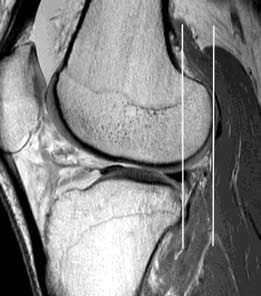

如图所示,胫骨平移的前移,可测量平行于图片框架的两条线(白线)之间的距离。在股骨外侧髁的正中矢状面上,通过胫骨外侧平台的最后角画一条线,第二条线与股骨外侧髁的最后面相切。胫骨前移位5-7mm提示前十字韧带撕裂,大于7mm可诊断为前交叉断裂。